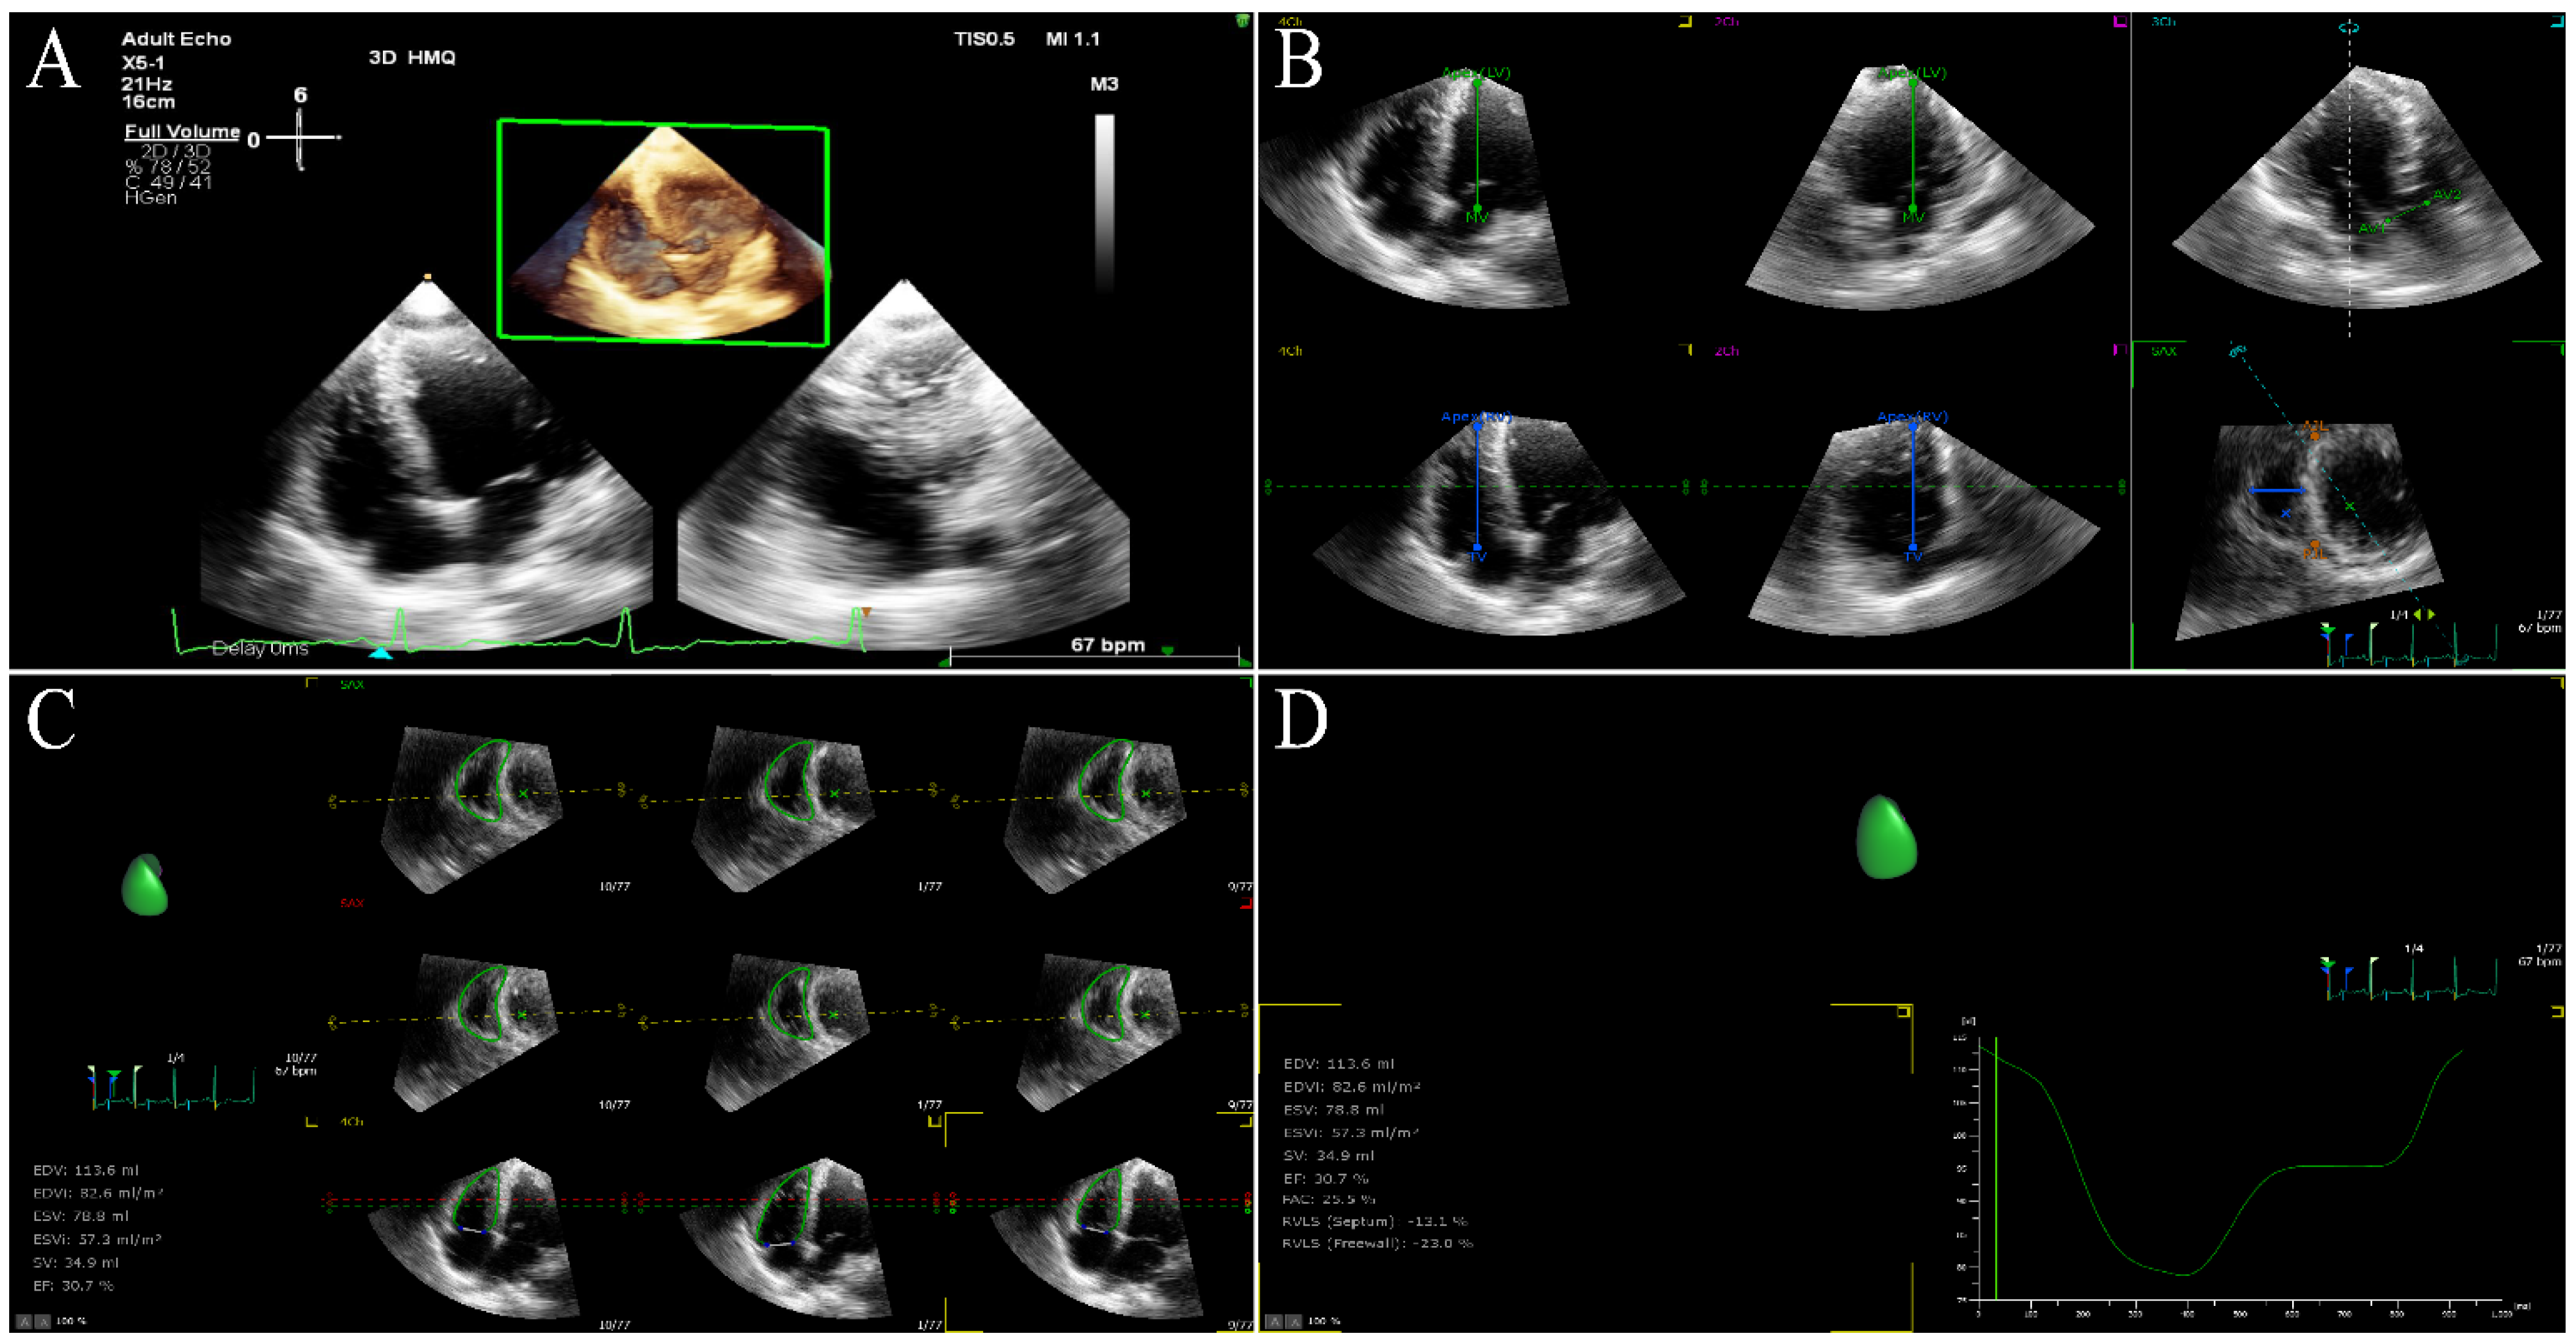

6.6. Right Ventricular Function

6.7. Myocardial Fibrosis